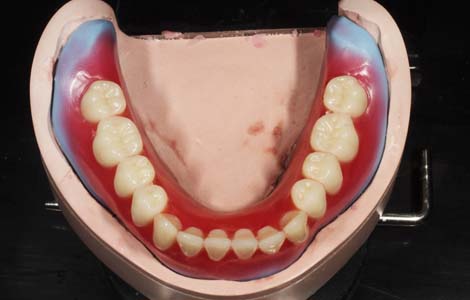

歯を1個1個並べていく

人工歯は、1本1本並べていきます。既に歯は無くなっていますので、お口の中の形からどこに並べるかを想像するしかありません。とても重要な作業もあり、非常に難しい作業でもあります。10人の歯科医がいれば10通りの歯並びができるといっても過言ではありません。

噛み合わせ・審美性・話しやすさ

すべてに配慮

人工歯を並べる位置は患者さんごとに異なります。そのため、人工歯は1本ずつ分かれていて、自由に配置できるようになっているのです。術者の知識と技術がもっとも必要とされる作業です。患者さんに満足して頂ける入れ歯を作るには(1)噛み合わせ (2)審美性 (3)話しやすさをすべて満たさなければなりません。これらを総合的に配慮しながら入れ歯を作ることで、より元の歯に近い噛み心地を提供できるのです。